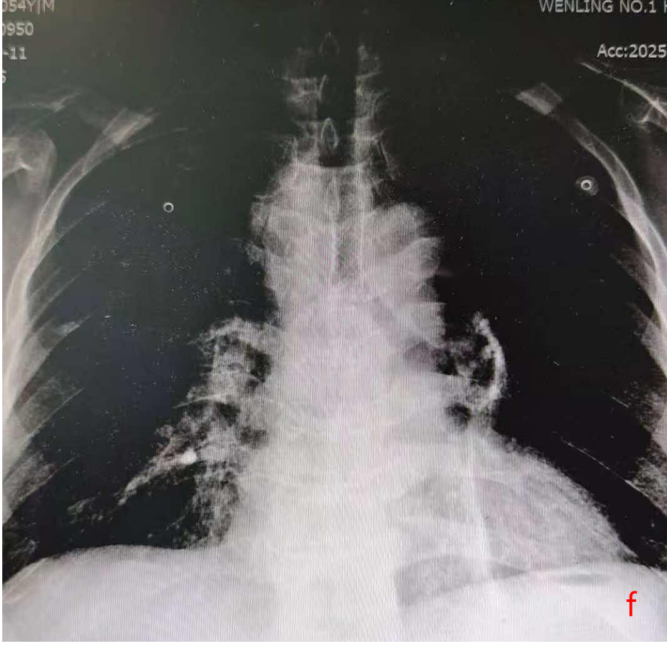

意外却在2025年9月悄然发生。当时W先生正在外院准备接受放疗,期间呼吸困难症状急剧加重,不仅无法耐受下床活动,还伴随咳嗽咳白黏痰。紧急复查CT显示,他的气管下段已出现重度狭窄,这一状况不仅严重威胁生命安全,也让原本的放疗计划因风险过高而难以实施。危急时刻,W先生前往温岭市第一人民医院寻求进一步救治。

2025年10月10日,手术在全麻下顺利开展。医护团队通过支气管镜的精准引导,将支架成功植入患者气管狭窄部位,整个过程平稳有序。术后奇迹很快显现:W先生的呼吸困难症状当场明显缓解,复查胸片提示气道下段通畅度显著改善,没过多久便能正常进行日常活动。短暂恢复后,他顺利返回继续接受胸部肿瘤放疗,整个放疗过程进展顺利,胸部肿瘤明显缩小。